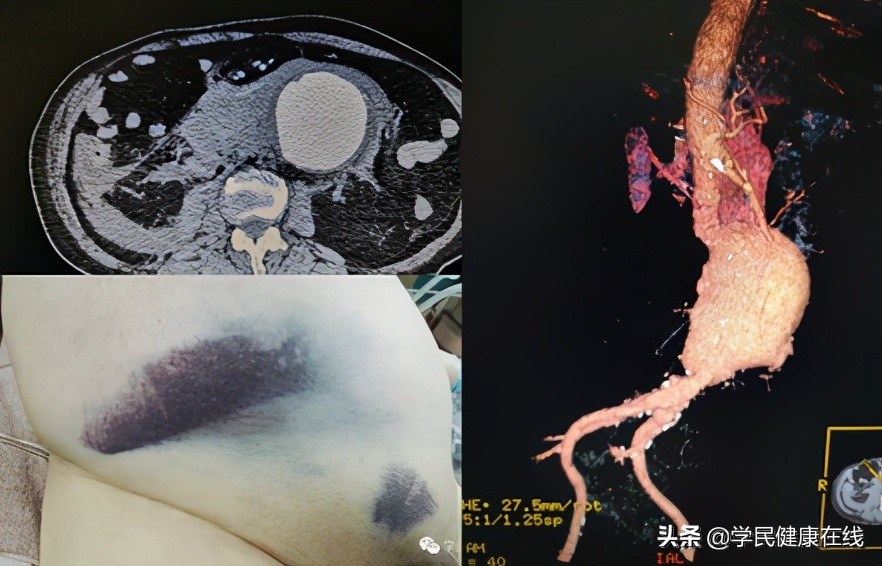

图1.破裂的腹主动脉瘤